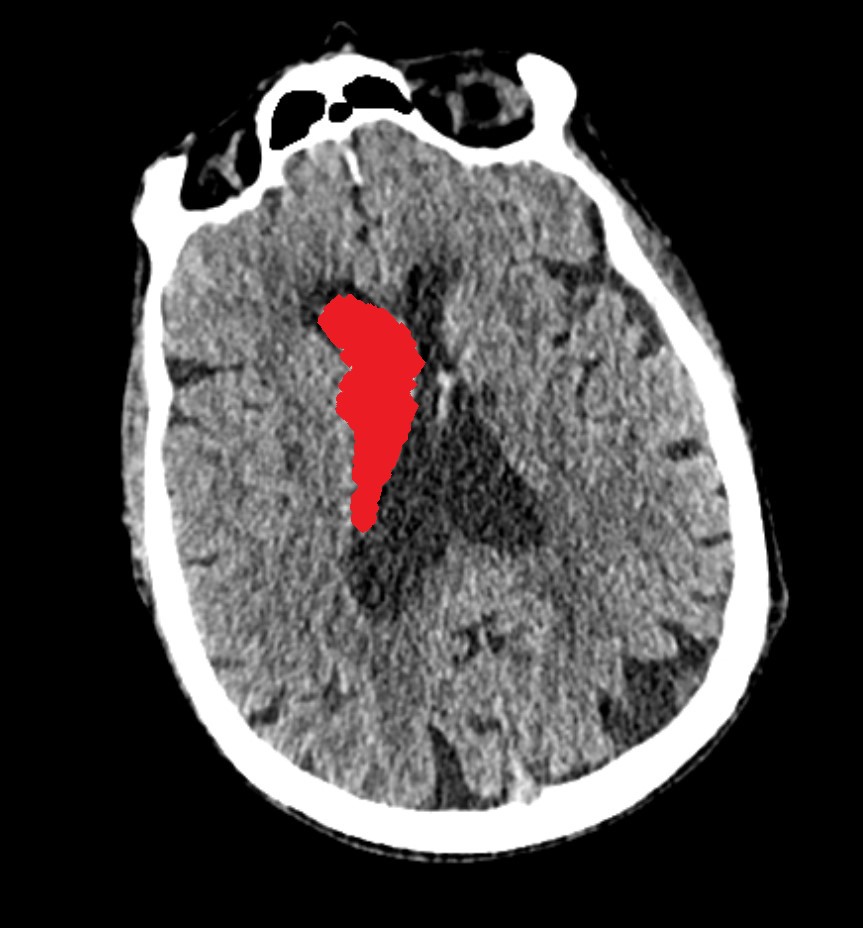

Intraventricular Hemorrhage

This is an Intraventricular Hemorrhage (IVH). The ventricles are spaces in your brain where the protective fluid (called cerebrospinal fluid) is made. Damage to the small arteries around the ventricles is usually the cause of this type of injury. On a CT scan, your doctor may identify blood inside the ventricles. When there is blood in this area, there is often bleeding in other parts of your brain. It may require the placement of an external ventricle drain (called an EVD) to relieve the pressure on your brain.